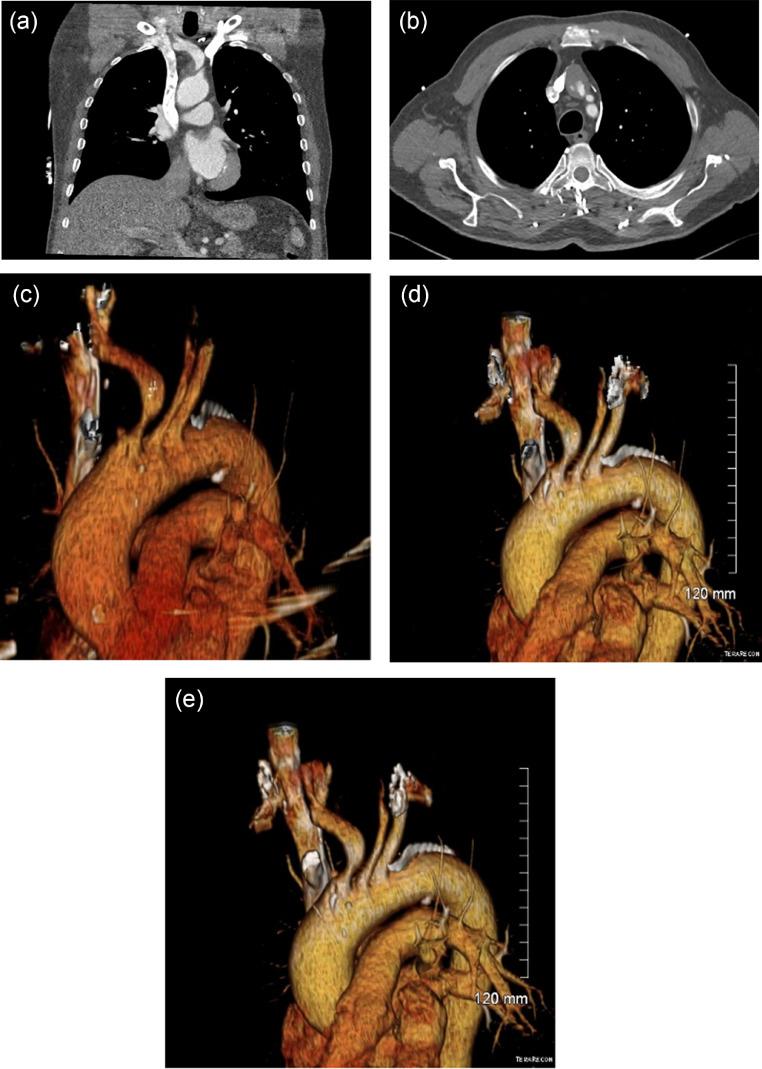

A 70 year old left-handed man presented to his general practitioner with abnormal left arm movements, left hemianopia and loss of balance. He was found to have an isolated brachiocephalic artery aneurysm, measuring 3.5 cm, with associated plaque rupture, contributing to recurrent episodes of transient ischemic attack. He was discussed extensively by a multidisciplinary team. e concurrently had complete occlusion of the right internal carotid artery with distal reconstitution in its supraclinoid segment from collaterals. Stenting of the region would necessitate inappropriately covering the right vertebral artery which would further compromise intracerebral blood. Surgical intervention was deemed the only safe option and he was thus accepted for cardiothoracic surgery. Standard workup revealed left anterior descending artery stenosis. He underwent coronary artery bypass grafting, left atrial appendectomy and brachiocephalic artery resection with replacement with a interposition graft with 10 mm polytetrafluoroethylene graft. He recovered well. This case demonstrates the multi-disciplinary decision making in a rare cause of embolic stroke.

一名70岁的左利手男性因左臂异常运动、左侧偏盲和平衡能力丧失就诊于他的全科医生。检查发现他有一个孤立的头臂动脉动脉瘤,直径3.5厘米,伴有斑块破裂,导致短暂性脑缺血发作反复发作。多学科团队对他进行了广泛讨论。他同时右侧颈内动脉完全闭塞,其床突上段通过侧支循环实现了远端再通。对该区域进行支架置入将不可避免地覆盖右侧椎动脉,这将进一步损害脑内血液供应。手术干预被认为是唯一安全的选择,因此他被接受进行心胸外科手术。标准检查显示左前降支动脉狭窄。他接受了冠状动脉搭桥术、左心耳切除术和头臂动脉切除术,并用10毫米聚四氟乙烯移植物进行了间置移植替代。他恢复良好。本病例展示了在栓塞性中风罕见病因中的多学科决策过程。